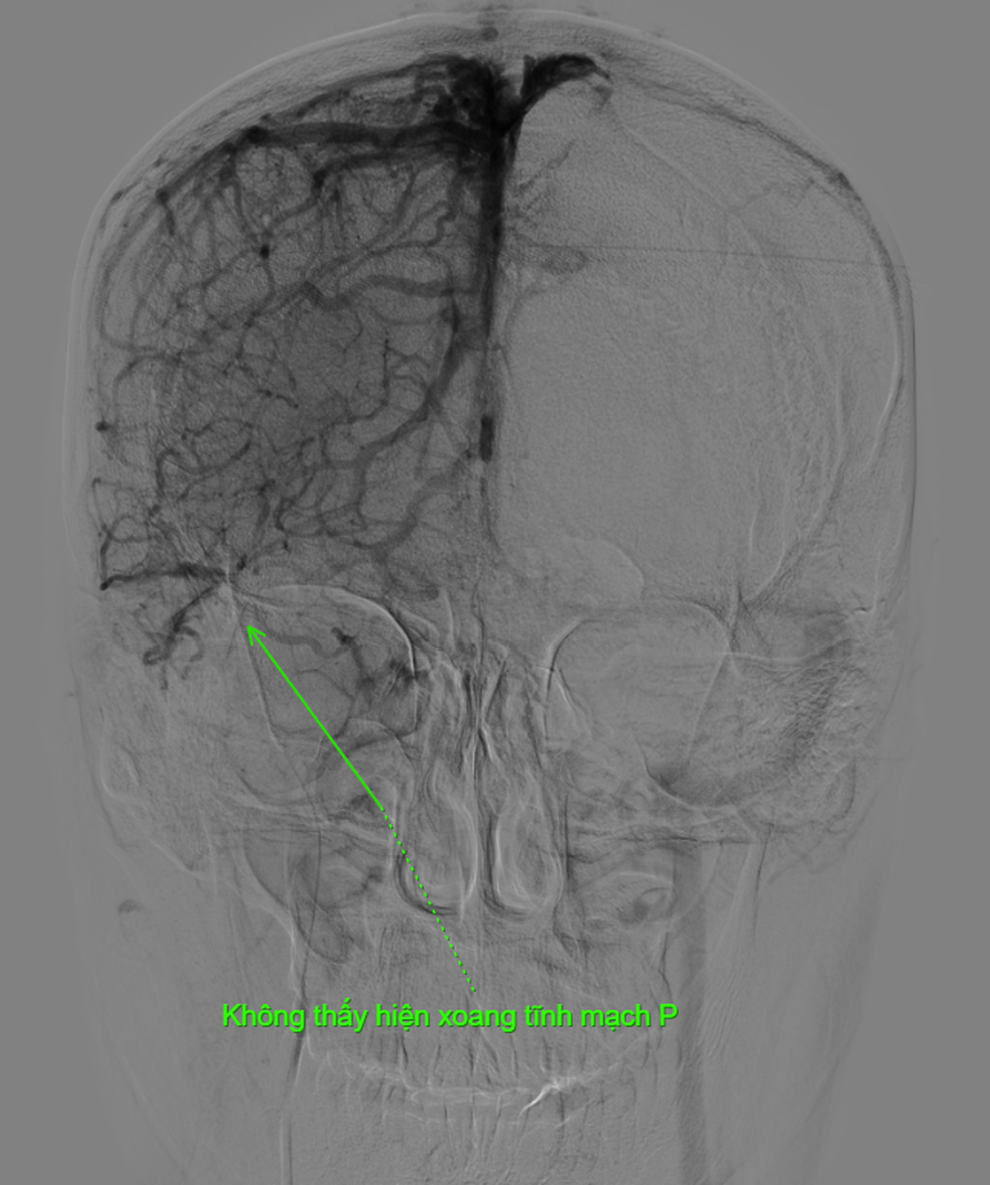

Kết quả phim chụp tại Bệnh viện Việt Đức cho thấy bệnh nhân bị tắc gần như toàn bộ hệ thống tĩnh mạch dẫn lưu não, bao gồm xoang dọc trên, xoang ngang, xoang sigma và đoạn đầu xoang tĩnh mạch cảnh trong phải.

Bác sĩ Đào Xuân Hải - Khoa Chẩn đoán hình ảnh, Bệnh viện Việt Đức cho biết, đa số bệnh nhân huyết khối tĩnh mạch não đáp ứng tốt với điều trị nội khoa nhưng trường hợp này huyết khối rất lớn, tắc hoàn toàn các xoang tĩnh mạch lớn và diễn tiến xấu đi dù đã dùng thuốc.

Sau khi xác định vị trí huyết khối trên máy DSA, các bác sĩ dùng hệ thống dụng cụ được đưa từ tĩnh mạch đùi lên tĩnh mạch cảnh trong phải để lấy huyết khối từ tĩnh mạch cảnh trong lên đến xoang dọc trên - vị trí có huyết khối. Từ đây, bác sĩ lấy toàn bộ huyết khối từ xoang dọc trên xuống tĩnh mạch cảnh trong để tái thông hệ thống xoang tĩnh mạch não.